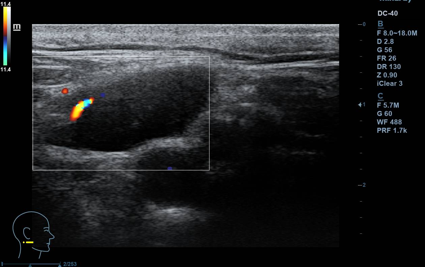

Lesión hipoecogénica cervical de aspecto sólido, de 2,5 x 1 cm (ancho x alto), con hilio vascular que preserva, impresiona de residual, vascularizado (Doppler). Otras lesiones similares de menor tamaño, pero con hilio mejor preservado, de aspecto benigno. Todas las lesiones impresionan de adenopatías. A nivel contralateral: lesiones similares en menor cuantía, también de aspecto benigno. Tiroides normal.